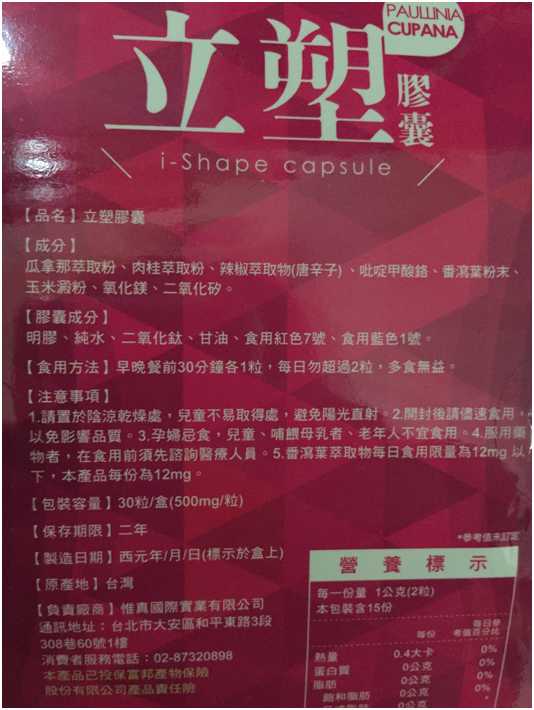

Supercut塑魔纖立塑膠囊的成分有:瓜拿那萃取粉、肉桂萃取粉、辣椒萃取物(唐辛子)、吡啶甲酸鉻、番瀉葉粉末、玉米澱粉、氧化鎂、二氧化矽。

之前上過相關課程,成分表是依照每項成分的多寡來排列順序,排在最前面的就是產品的主要成分!

那我就跟大家分享瓜拿那萃取粉、肉桂萃取粉和辣椒萃取物吧

瓜拿那萃取和辣椒萃取是可以幫助纖體瘦身常見的營養素!

1.「瓜拿那」是原產於亞馬遜流域的一種藤蔓植物,富含酵素可以幫助排便順暢,並且能抑制脂肪分解酵素,此外也有降低食慾的效果喔~~萃取物中含有天然咖啡因,可以提高新陳代謝率以及排出多餘水分!

2.「辣椒萃取物」則是可以幫助體內脂肪燃燒、增加卡路里的消耗,達到防止脂肪積聚的效果

3.「肉桂萃取物」看到肉桂,就想到麥當勞的蘋果派或是手掌麵包,雖然很多人很害怕那味道,但艾哥愛死肉桂了!!!!肉桂在古代被視為是最有價值的東方香料之ㄧ,中世紀時,肉桂的聲望僅次於昂貴的黑胡椒,除了香料和薰香價值, 傳統上肉也被用來治療消化不良、脹氣、關節疼痛、出血和經痛,研究也指出肉桂可以促進新陳代謝喔

食用方式:早晚餐前30分鐘各1粒,每日不超過2粒。(多食無益)

番瀉葉萃取物每日食用限量為12mg以下,